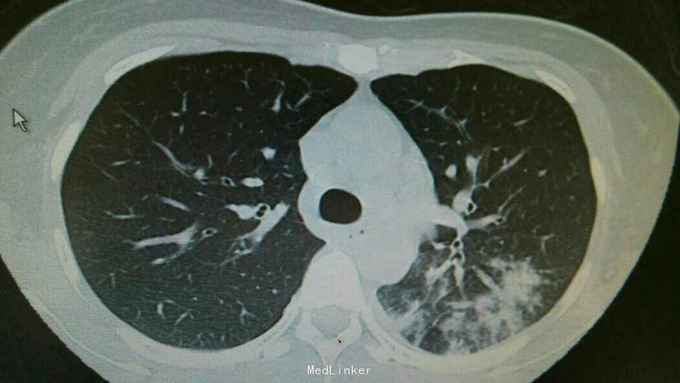

主诉:发热伴咳嗽咳痰6天。 病史:患者6天前无明显诱因出现发热,最高体温39.3度,伴有咳嗽,咳痰,咳黄色粘液痰,无畏寒寒战,无头晕头痛,为求治疗,入住我科。

查体:双肺呼吸音粗,双下肺可闻及湿罗音。心腹无异常。 辅查:双肺炎症,左侧可见多发斑片状,渗出实变影,边缘模糊,部分邻近胸膜,粘连。

诊断:肺炎支原体费炎。 治疗:入院予以抗感染,止咳化痰等治疗。治疗后复查胸片,左中下肺炎症好转。